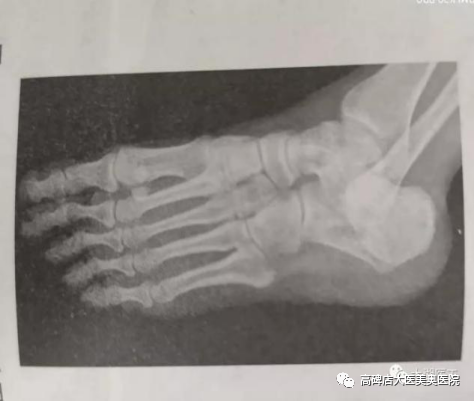

足前后位受检者坐于摄影台上,受检侧膝关节弯曲,足底紧贴探测器。

足内斜位受检者坐于摄影台上,受检侧膝部弯曲向内倾斜,足底内缘紧贴探测器,足底与探测器呈30°~45°角。

足前后位

足内斜位